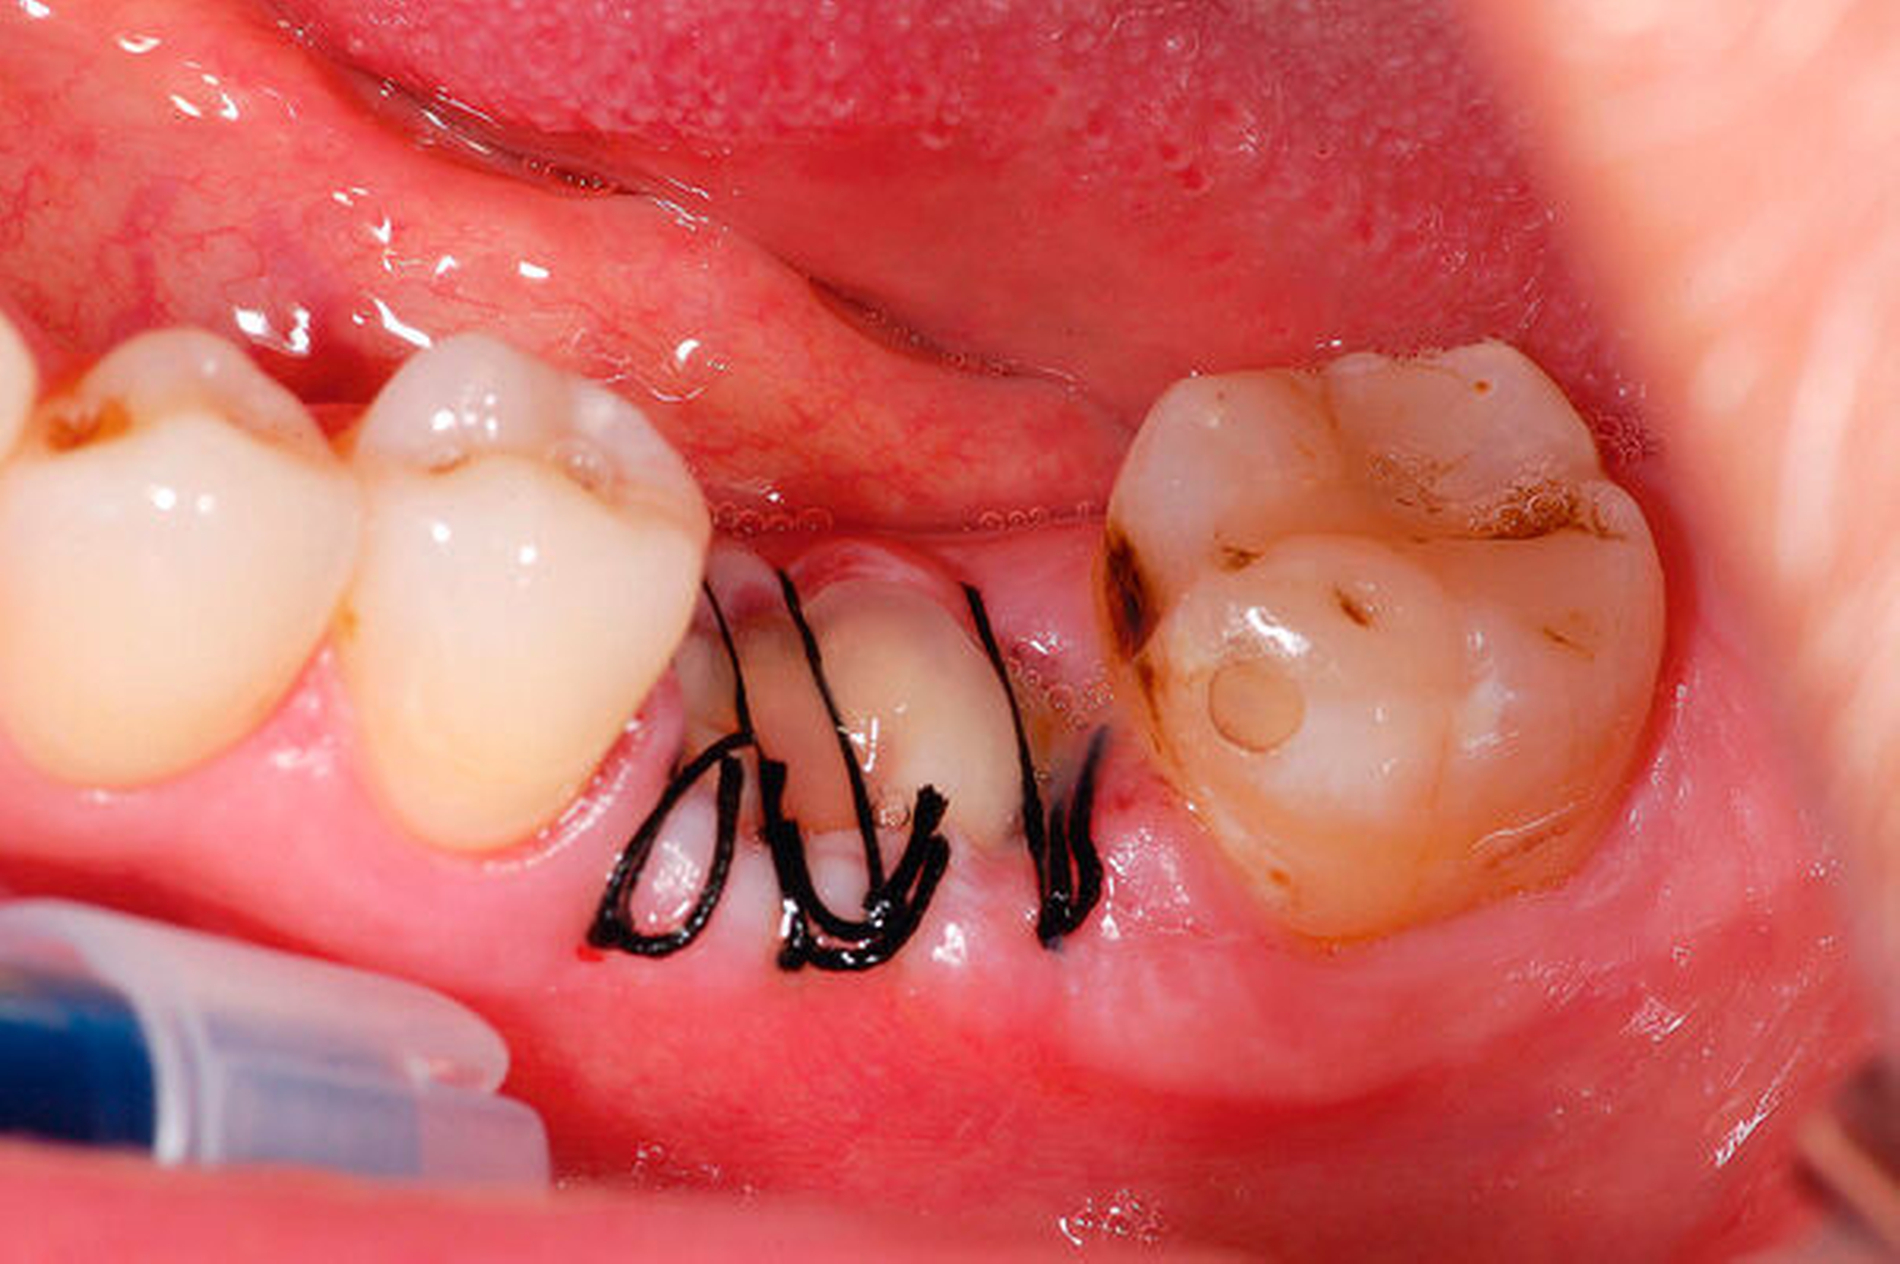

Parodontale Regeneration

Zahlreiche prä-/klinische Studien haben in den vergangenen Jahrzehnten gezeigt, dass eine Vielzahl klinischer Protokolle zur parodontalen Regeneration beitragen und die klinischen Ergebnisse bei vertikalen parodontalen Knochendefekten und bei Furkationsdefekten Grad II verbessern kann. All diese Erkenntnisse sind in die aktuelle S3-Leitlinie zur PAR-Therapie eingeflossen, die klare Empfehlungen gibt, wann und wie regenerative Maßnahmen in der Therapiestufe 3 angewendet werden sollten.